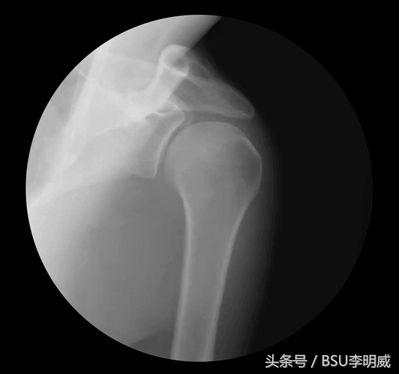

那今天我们讲什么呢?给大家准备的是一种慢性损伤中比较常见的损伤机制,困扰着很多人,接下来我们就讲讲这种烦人又反复出现的疼痛——肩关节撞击综合症

这三块骨头在完成肩膀所有的运动中配合紧密,各司其职,每一块骨头都有自己的作用和活动范围,所以当其中的一块骨头(比如肩胛骨)没有干自己该干的那部分工作的时候,其他的部位(肱骨)就需要承受更多的负担,就更容易损伤;并且,在其中一块骨头(比如肩胛骨)没有干自己的活的同时,它也就不会挪地方了,其他的骨头(比如肱骨)上来的时候自然而然没有了空余的空间,和它撞在了一起。当你的胳膊活动很大,并且速度很快的时候,那么撞击的程度就会比较重;如果你活动的范围不是很大,平时的活动不是很剧烈,但是每次微小的撞击会慢慢累加起来,造成之后持续的疼痛。

当肩胛骨向上旋转的幅度不够的时候,你如果继续将手臂举高,肱骨头就很容易撞到肩胛骨的肩峰上了。所以这其中肩胛骨的向外旋转是极其重要的。

在肩膀上举的过程中,三角肌将肱骨头向上拽,而冈下肌、小圆肌、肩胛下肌、冈上肌将肱骨头向下拽,并产生滑动和转动,使我们的肱骨头始终和肩胛骨的肩峰保持一个合理的距离。